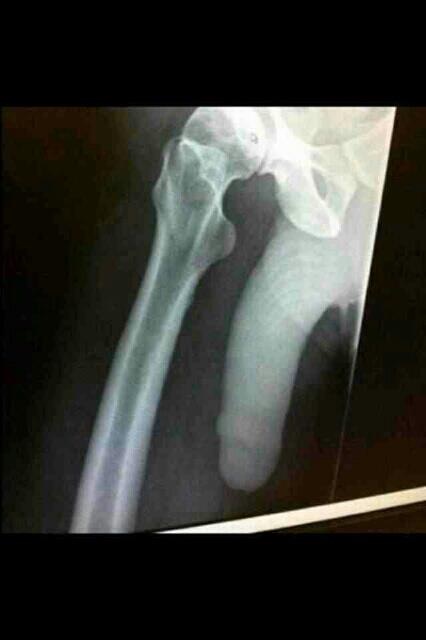

fell over a few months ago and cracked me hip,this is the xray

Someone seems to have stuck their thumb in the x-ray.